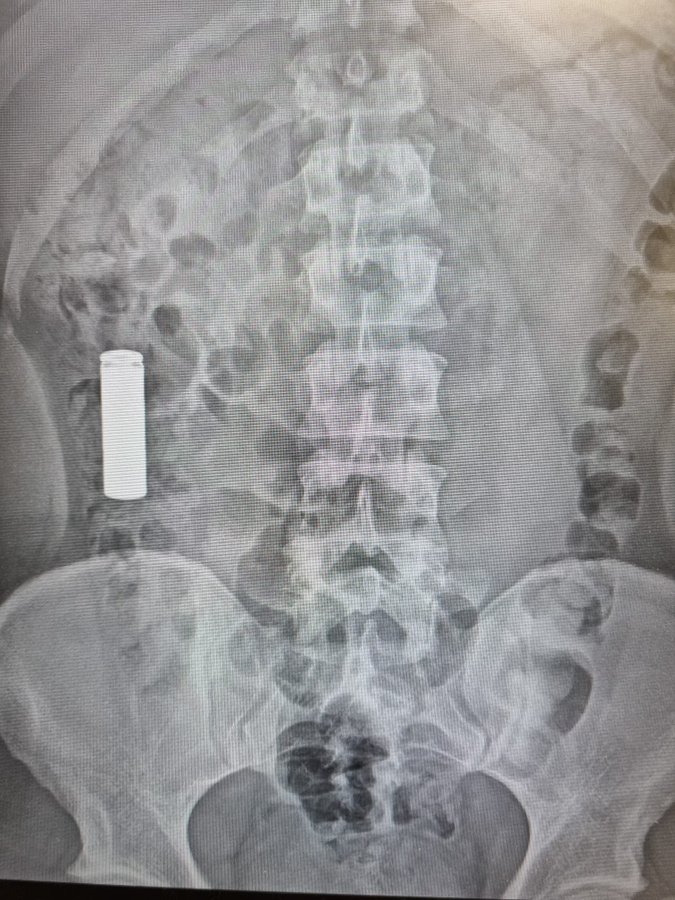

No es fácil pillar a ilegales por las calles. Nadie va diciendo quién es ilegal o quién no. En los hospitales cuentan un caso común. Llega una persona que se ha tragado una pila... y ve su plazo de estancia en España ampliado 90 días... con lo que la deportación se aplaza; y cuando pase el plazo podrá esperar otra circunstancia desgraciada en la que le pillen como ilegal... y comienza el proceso de tragarse otra pila. Dicen que son las ONG las que asesoran así: